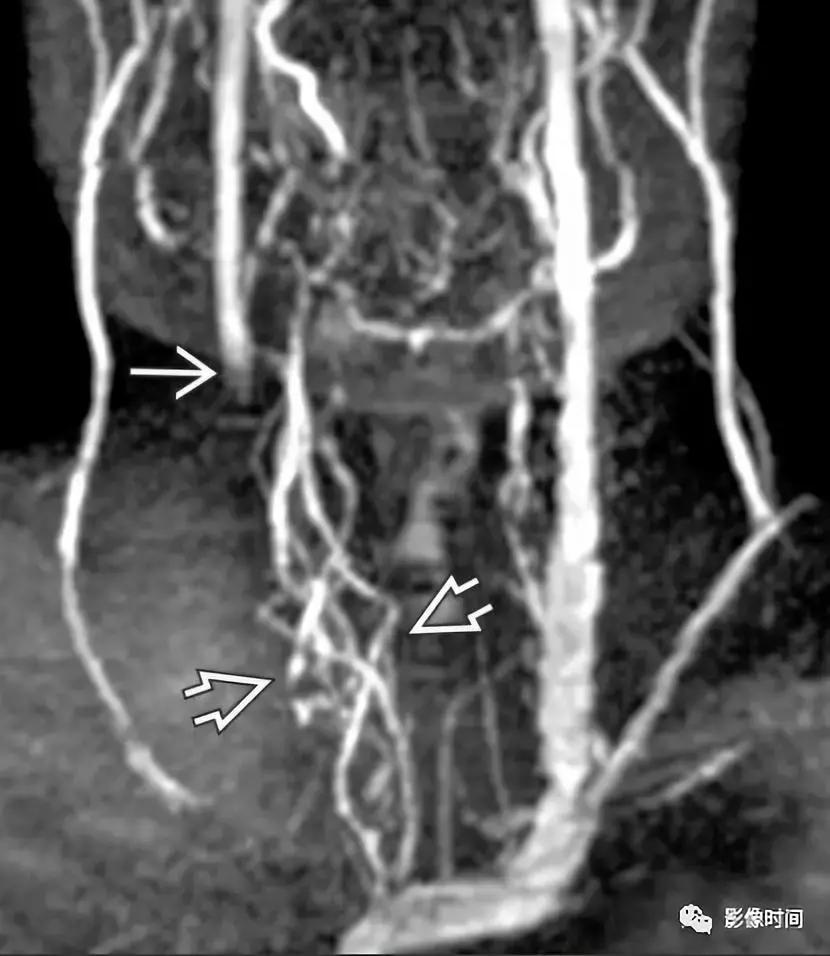

颈部 CT 增强显示右侧 PICC 术后,右侧颈内静脉血栓形成,另可见静脉壁强化和左颈内静脉未闭时管腔造影剂填充。MRV 原始图像显示另一患者右侧乙状窦向颈内静脉延续的血栓,MRV 显示右侧颈内静脉闭塞,周围多发迂曲纤细静脉影,提示慢性代偿。